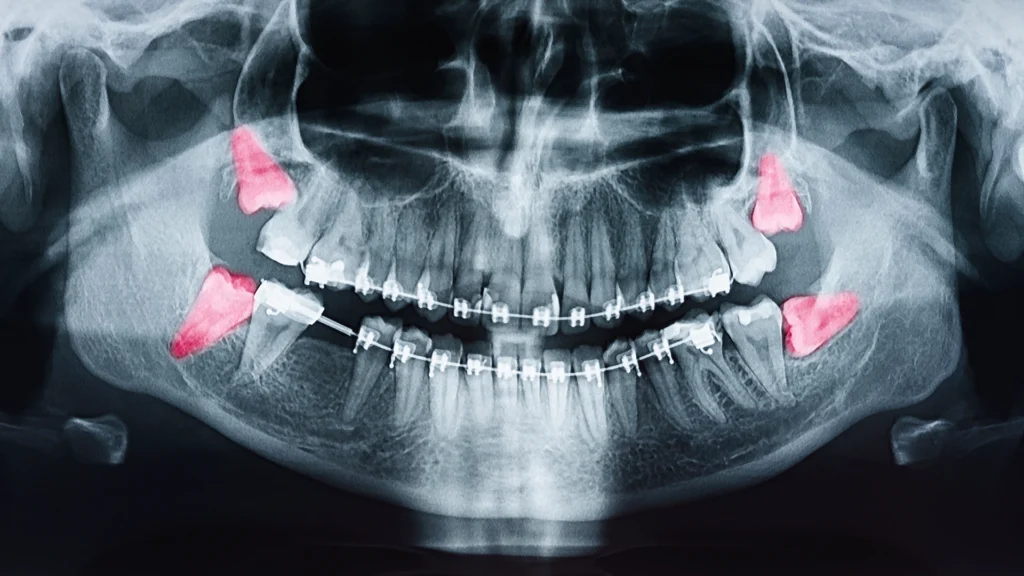

Talán nem meglepő, hogy a folyamat a részletes diagnosztikával indul. Ez általában egy panoráma röntgenfelvételt és sokszor y háromdimenziós CBCT-felvételt is magában foglal. Ezek a képek megmutatják a fog pontos helyzetét, a gyökerek alakját, a csontban való elhelyezkedést, valamint a környező anatómiai képletek, az idegek és az arcüreg viszonyát. A szájsebész ezek alapján tervezi meg a beavatkozás pontos menetét.